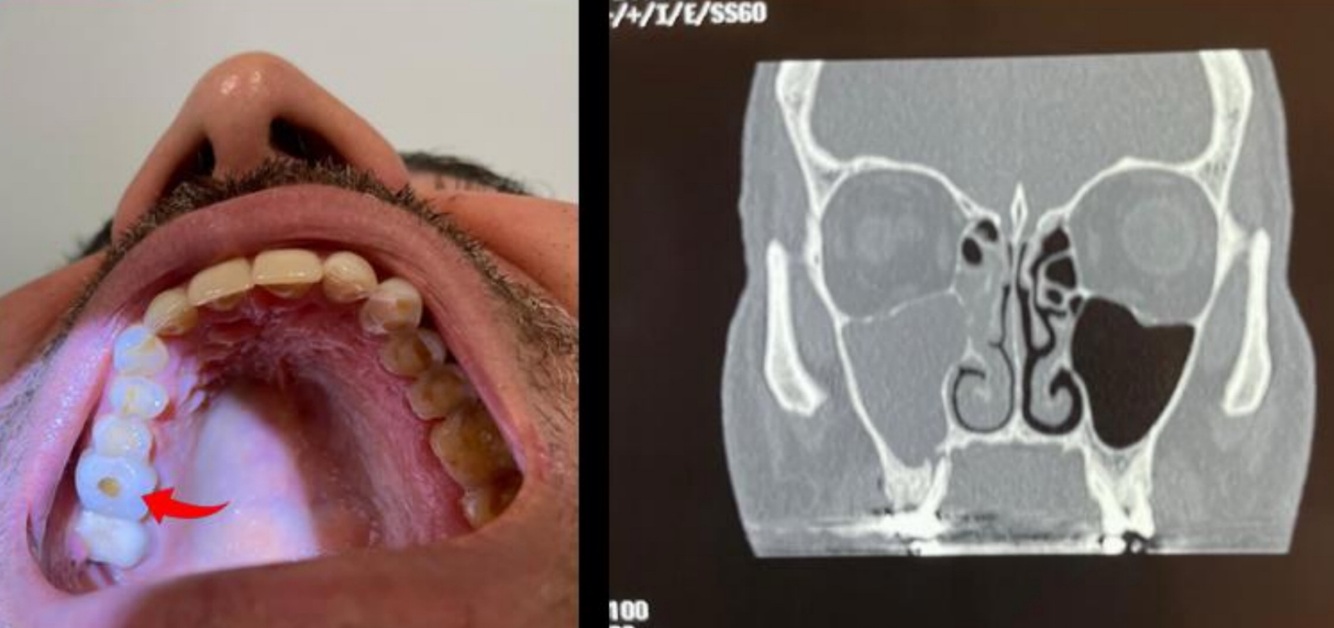

¿Qué es esto?

Comunicación oro-antral